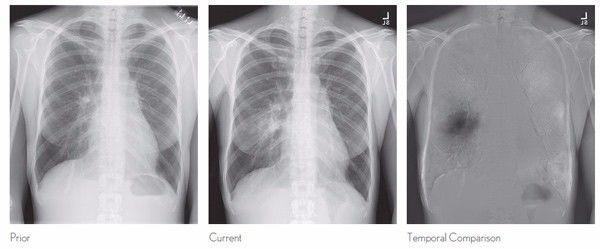

在医疗领域,尤其是皮肤病检测,图像识别也很重要。用户可以拍摄照片,获得初步诊断。斯坦福大学的研究人员开发了可以发现皮肤癌的算法。根据结果,其诊断皮肤癌的效率与专业医生相当。该算法并未投入生产,仍有商业机会。我们也期待医疗保健app的出现,特别是x射线诊断和超声诊断,以及可以通过图片诊断糖尿病患者不能吃哪些食物。微软、谷歌、亚马逊提供的云服务消除了开发人员将计算机视觉应用生产的障碍。